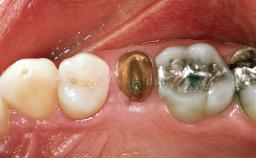

In November 2001, a 53-year-old female presented seeking advice and options for treatment of her maxillary incisor teeth. She was dissatisfied with both the functional and esthetic qualities of her existing restorations. Her medical health was excellent, and she reported no contraindications to dental care. On presentation, the patient’s dental health was less than ideal. Although she had no probing depths greater than 3 mm, she suffered from generalized chronic adult periodontitis and displayed multiple sites of bleeding on probing. Her remaining dentition was heavily restored, and many teeth had been endodontically treated. Areas of recurrent dental caries were noted on many teeth. Radiographically and clinically, the maxillary incisor teeth exhibited large areas of active caries, and after the splinted crowns had been removed, the teeth were determined to be non-restorable.